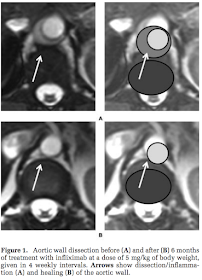

IFX 5mg/kg q4w にて、6ヶ月後には壁肥厚が消失